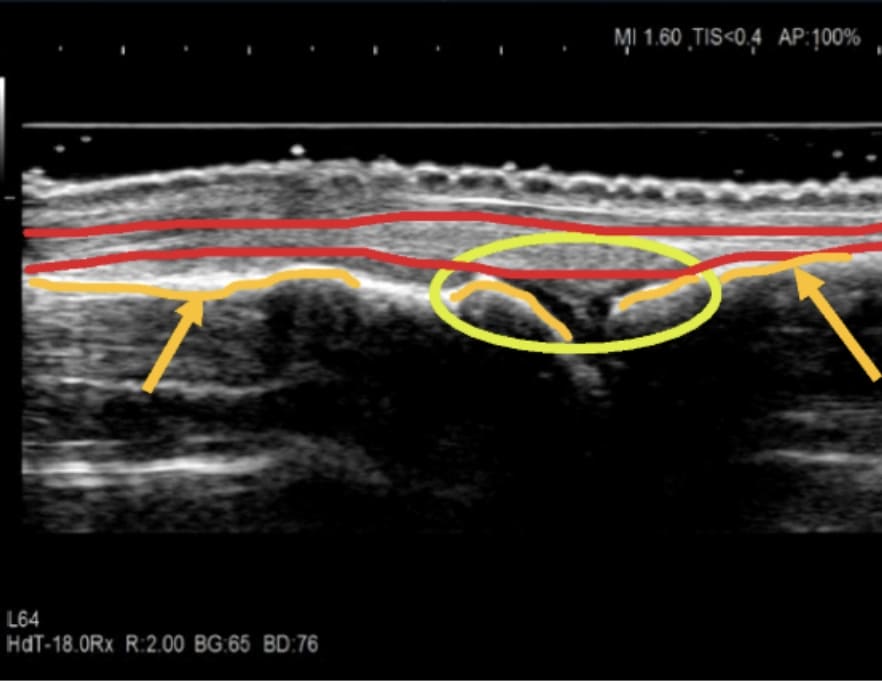

関節リウマチは、関節滑膜が炎症を起こすと厚みを持ち(滑膜肥厚)、滑膜内には異常な血流として示されます(滑膜炎)。これらを「関節エコーガイドライン」に沿って評価し治療に反映しています。

超音波検査は視覚的に炎症が確認でき患者様にもリアルタイムで画像を見てもらうことができるため関節リウマチの状態や治療効果を医師と一緒に共有することが出来ます。また、レントゲン画像では分からない小さな骨破壊(骨びらん)の確認も有用です。

関節エコーはレントゲン検査では診ることが出来ない滑膜、腱、筋肉などを観察しています。